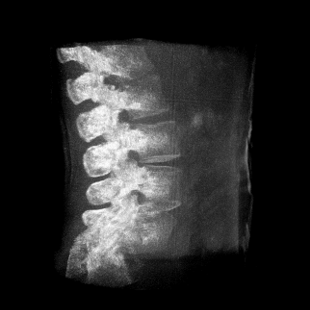

術(shù)中三維成像和橫斷面圖像提供多角度的手術(shù)診斷信息,輔助醫(yī)生進行術(shù)中評估判斷,諸如骨折復位情況和內(nèi)植入螺釘?shù)某叽绾臀恢茫o助手術(shù)更好地完成。

提供更大的術(shù)中三維成像視野,采集更多圖像信息,可一次拍全全段頸椎、全段腰椎、七節(jié)胸椎、雙側(cè)骶髂關(guān)節(jié)、股骨頭及單側(cè)盆骨。